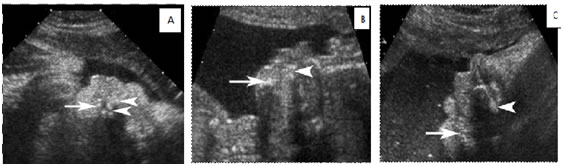

Problems associated with syngnathia include issues with the maintenance and protection of the airway, feeding difficulties and problems with anaesthesia management. Facial growth and development are also compromised. Surgical treatment has been described, but there is no established standard technique. Treatment is individualized, in terms of jaw function and outcome; it may be problematic incomplex cases. The prognosis of syngnathia type 2b is poor. No case of survival of syngnathia type 2b has been reported.1 Maxillomandibular fusion is diagnosed after birth when it is discovered that the infant cannot open his or her mouth. This unanticipated diagnosis can potentially result in major complications with airway management and feeding at birth. Thus, prenatal diagnosis in suspected cases can have great clinical implications in that necessary preparations for the tailored care of affected infants can be made before delivery to reduce the chances of infant morbidity and mortality. Multidisciplinary intervention at the birth is important to ensure a correct airway.6 Scant radiologic literature is available on radiologic findings of maxillomandibular fusion, almost all of which were postnatal imaging findings, such as computed tomography (CT).6 Ultrasound examination via a sagittal plane (Fig. 1) of the face can achieve an antenatal diagnosis, as well as its association with other malformations such as agenesis of corpus callosum.7 Laster et al5 showed one prenatal sonographic image depicting the absence of mouth opening and a contiguous appearance of the upper and lower jaws, although these findings did not lead to a prospective prenatal diagnosis in their case.5 In this report, we present the prenatal sonographic and magnetic resonance imaging (MRI) findings and with postnatal CT imaging, and review the existing literature. We discuss these findings with a focus on particular signs that may suggest the diagnosis of maxillomandibular fusion prenatally and thus allow appropriate prenatal planning to manage any potential complications at time of delivery. RADIOLOGICAL FINDINGS:

Figure 1: Sagittal plane of fetus where maxillomandibular bone fusion can be observed syngnathid 2b.

Figure 2: A, Sonogram of a fetus with maxillomandibular fusion showing lack of a normal gap between the mandible (arrow) and maxilla (arrowheads). Also note the small chin and protuberant lips in comparison with B and C. B and C, Sonograms of unaffected fetuses of the same gestational age with closed mouths. Note the substantial gap between the mandible (arrows) and maxilla (arrowheads) in both cases compared with A. Figure 3: The fetal MRI showing a small chin, a characteristically protruding jaw, and prominent, protruding lips Figure 4: Postnatal CT of the affected neonate. A, Postnatal off midline sagittal head CT showing fusion (black arrow) of the mandible (white arrow) and maxilla (arrowhead). Fusion was seen on multiple slices, more easily visualized on the 3D CT reconstruction (B). B, Postnatal 3D CT reconstruction of facial bones. Sagittal view depicts fusion of the maxilla and the mandible. The fusion in this case involved bilateral bony fusion of the mandibular and maxillary alveolar processes, with a small anterior slit remaining. The fusion also included fusion of the proximal parts of the mandibles, the ascending rami, to the posterior portions of the maxillas and to the zygomas bilaterally. However, the ascending rami of the mandibles were not fused to the zygomatic processes (asterisk) on either side. The coronoid processes of the mandible (arrowhead) are visualized, pointing to the most proximal aspect of the mandible. T indicates temporal bone; and Z, zygomatic bone. The dotted line represents the expected area of separation between the mandible and the maxilla. DISCUSSION Maxillomandibular fusion has always been an unanticipated diagnosis made at birth. Given that congenital oral cavity deformities have potential for causing difficult airway and respiratory impairment, prenatal diagnosis would allow appropriate preparation of staff for airway management at the time of delivery. Given the advanced imaging techniques available today, such as real-time sonography and fast sequences for fetal MRI, maxillomandibular fusion can potentially be detected prenatally.6 The reported sonographic findings in a case of maxillomandibular fusion, were an absence of mouth opening and a contiguous appearance of the upper and lower jaws. In normal fetus, there is normally a gap between the maxilla and mandible on sonography. Various studies have reported real-time sonography as a reliable method for the evaluation of fetal movement, particularly fetal facial expressions, in the second and third trimesters.8 These studies reported mouth opening in the context of swallowing, suckling, chewing, and even yawning detected by real-time sonography in fetuses without abnormalities. According to these studies, continued observation by real-time sonography (for anywhere between 15 minutes and 2 hours, depending on the study) is a reliable and reproducible method for visualizing fetal mouth opening. One of the studies even reported regular mouth openings during fetal quiet and active sleep states.9 Because fetuses with maxillomandibular fusion are incapable of opening their mouths, real-time sonography can a definite method of excluding this rare disorder in suspected cases. Real-time sonography would be best performed during the second trimester for optimal visualization of the fetus. 3D and 4-dimensional (4D) sonography can also be valuable in suggesting or diagnosing maxillomandibular fusion prenatally. Numerous recently published articles emphasized that the interpretation of the fetal image, especially of the fetal face, is easier and faster with 3D images than with 2-dimensional (2D) images.10,11 Three dimensional sonography has the capability of showing planes of a section that cannot be obtained with 2D sonography and thus allows for a comprehensive evaluation of facial anatomy. Kurjak et al11 commented on the specific advantages of the assessment of the maxilla and mandible for the diagnosis of micrognathia and retrognathia. Surface-mode rendering, in which the surface within the volume of interest (generally the skin) can be seen without the underlying tissue, has proven very useful in the evaluation of facial abnormalities.10 In the case presented here, the facial characteristics visualized on the The fetal MRI shows the maxillary and mandibular tooth buds to be closely apposed without the intervening space seen in unaffected fetuses. MRI revealed an open mouth on most sequences in all fetuses without maxillomandibular fusion.5,6 MRI would likely have been identified on 3D sonography if performed during the second trimester. The maximum-rendering mode highlights the maximal echo (bone) information of a volume data set and is an ideal tool for the 3D reconstruction of bony structures. Generally, cranial bones, the ribs, and other curvilinear bones, which cannot be properly visualized in a single 2D plane, are better assessed in a maximum- mode projection.11 Selectively imaging the bones on sonography can undoubtedly add to the potential of sonography for suggesting or diagnosing bony maxillomandibular fusion. Finally, 4D sonography, by adding the temporal component (as a virtually live 3D image) in the surface-rendered mode, has been described as advantageous in accurate visualization of subtle and fast facial expressions.11 The use of 4D sonography to monitor small or fast jaw and mouth movements (complementary to real-time conventional 2D sonography) would also be of potential value in the evaluation of suspected cases of maxillomandibular fusion. Both the management and outcome of patients with bony maxillomandibular fusion have varied. The rarity of the condition makes standardization of treatment difficult.